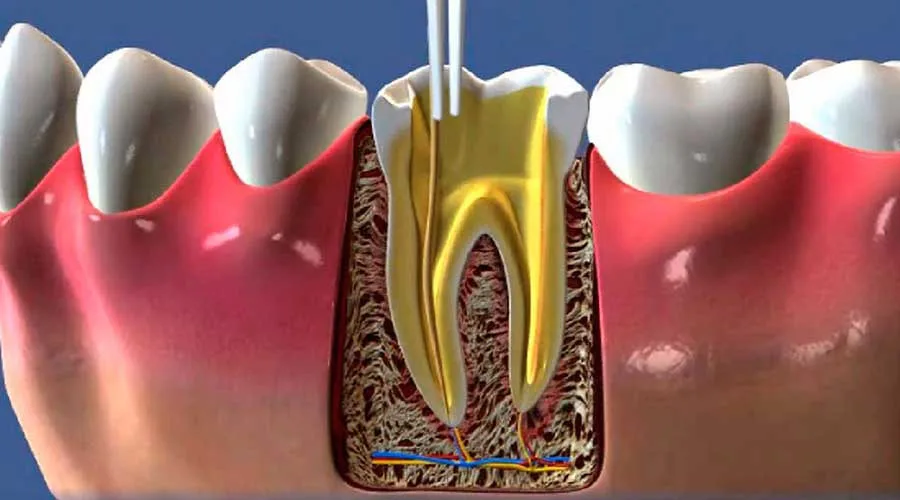

Buscar por um consultório endodontia perto de mim é uma decisão estratégica que une cuidado técnico e praticidade.

A proximidade facilita o acesso a tratamentos vitais, como o tratamento de canal, essencial para salvar dentes comprometidos e cessar quadros de dor aguda.

A praticidade nas consultas é um diferencial para quem possui uma agenda cheia. Visitar um consultório endodontia perto de mim permite que o tratamento não seja negligenciado, assegurando que a infecção seja removida e o dente preservado sem grandes alterações no seu roteiro diário.

Tecnologia Acessível: Unidades regionais modernas oferecem exames digitais e microscopia operatória;